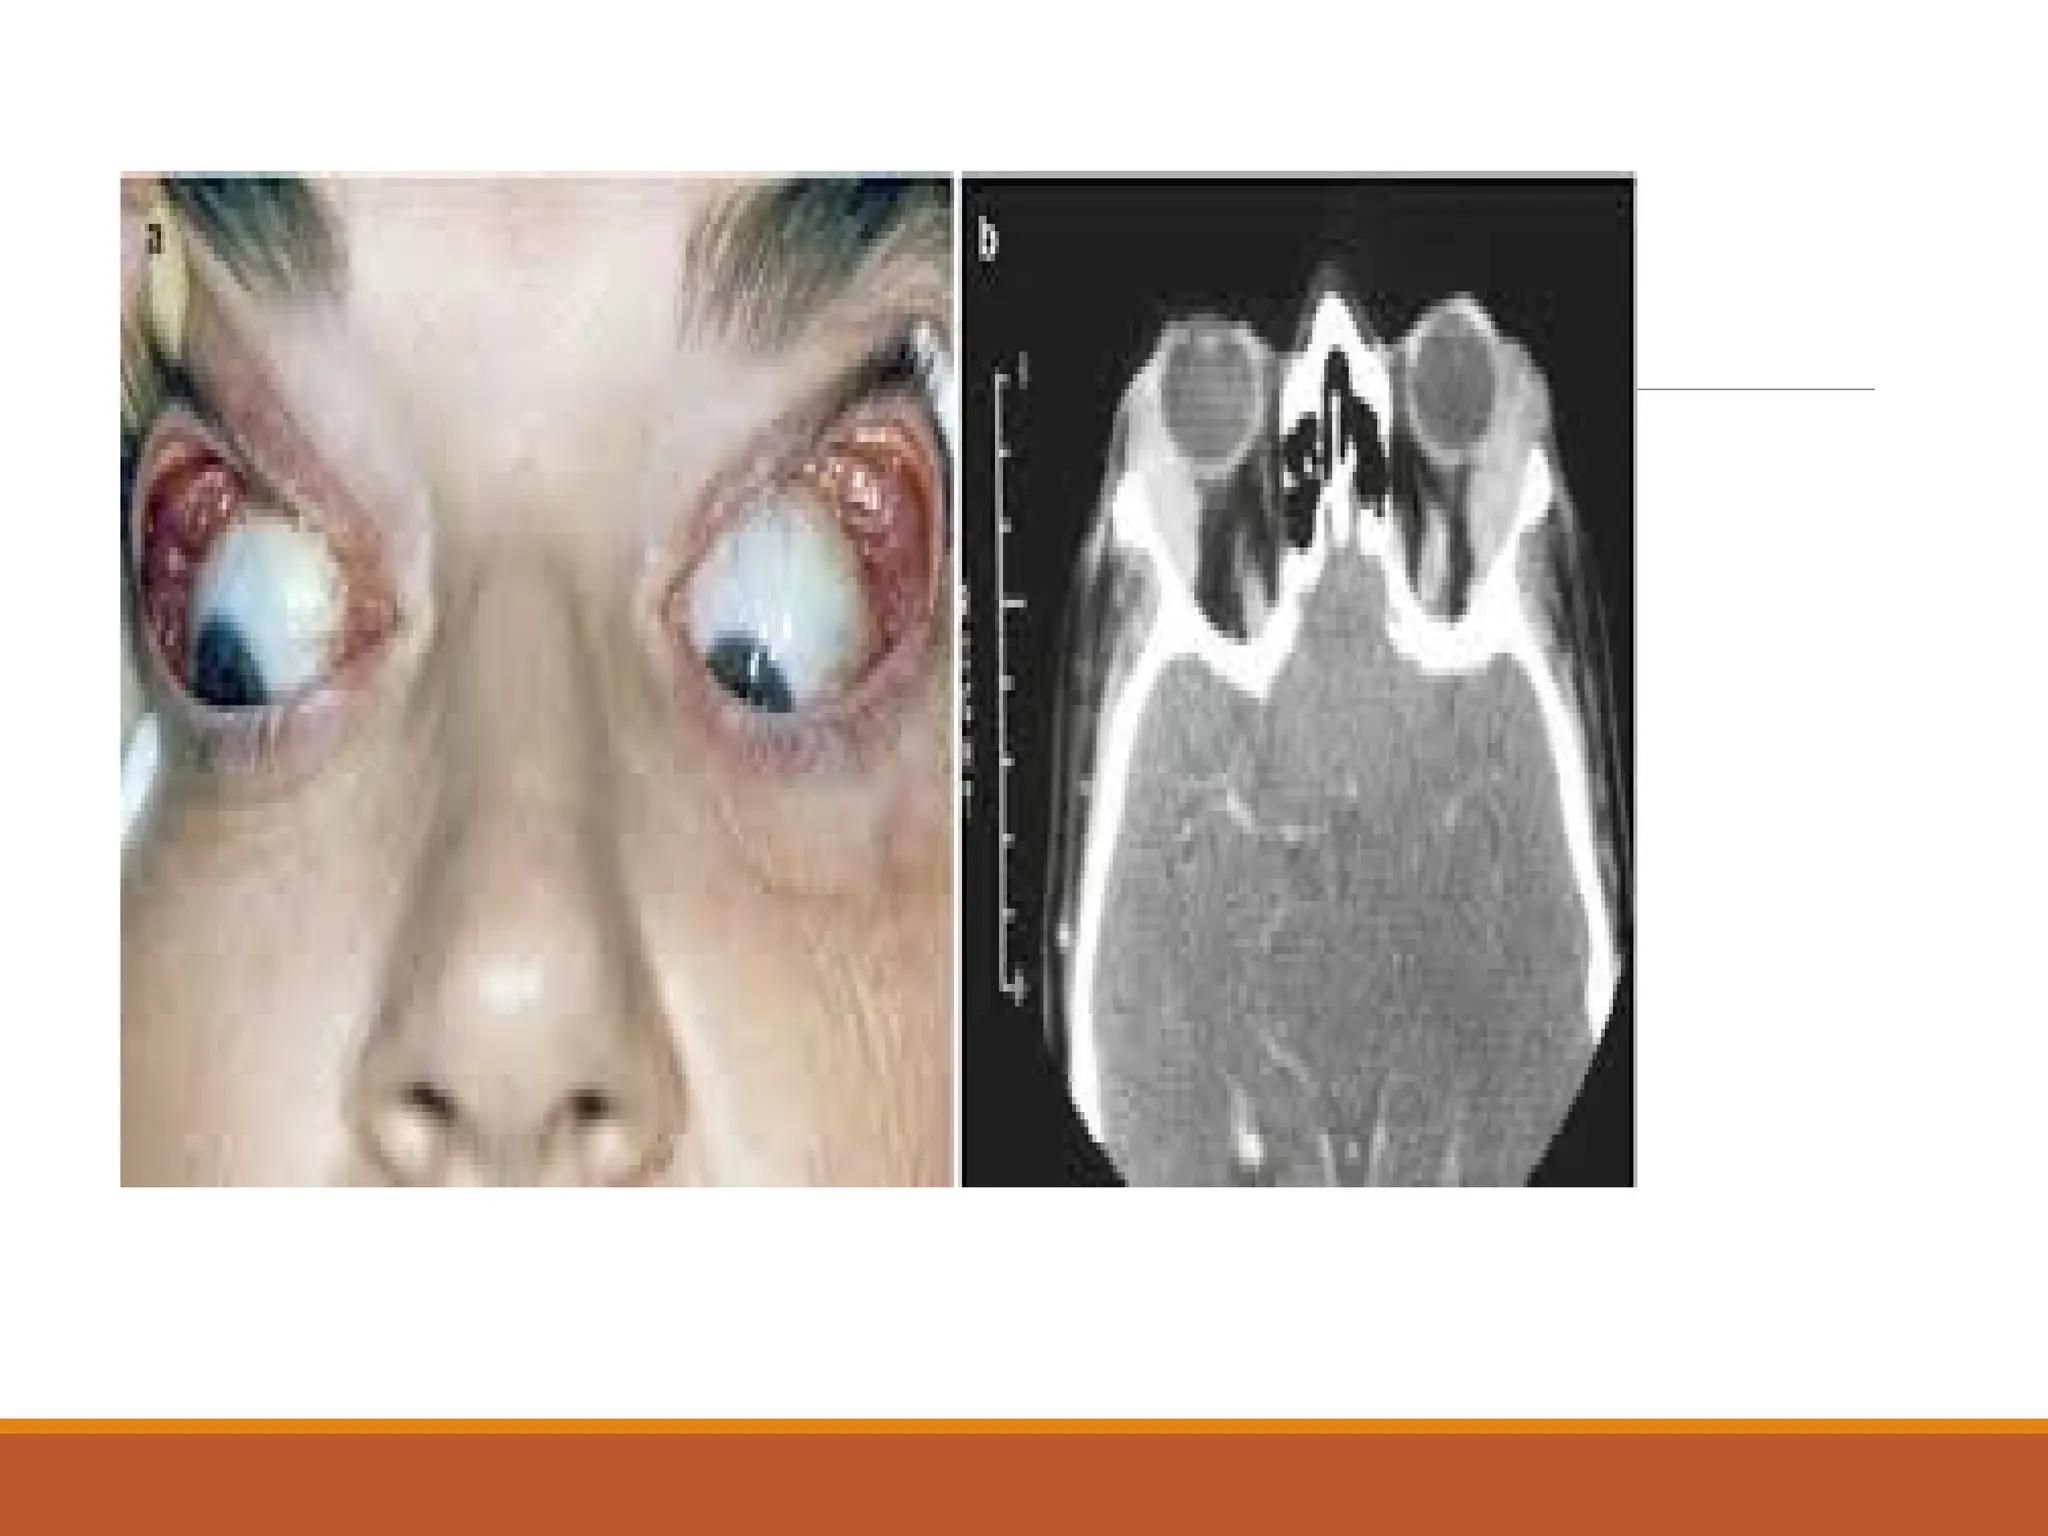

Clinical

Evidence of trauma-bleedng,fever,lid edema and rhinorrhoea.

Pain,headache,loss of vision

Tenderness,black eye,proptosis

Orbit and carvenoussinus Cellulitis-pre septal anterior orbit septum and post septal-orbital contents Serious-loss of sight and spread to carvenous sinus leading to thrombosis and death,

Clinical Evidence of trauma-bleedng,fever,lidedema and rhinorrhoea. Pain,headache,loss of vision Tenderness,black eye,proptosis